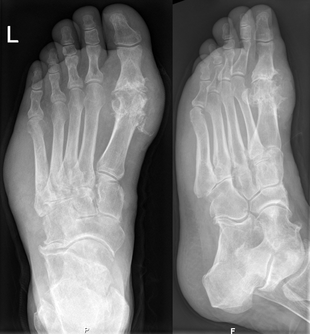

Gout may be diagnosed and treated without further investigations in someone with hyperuricemia and the classic acute arthritis of the base of the great toe (known as podagra). Synovial fluid analysis should be done, however, if the diagnosis is in doubt.[9] X-rays, while useful for identifying chronic gout, have little utility in acute attacks.[5]

Gout of the right MP joint of the big toe